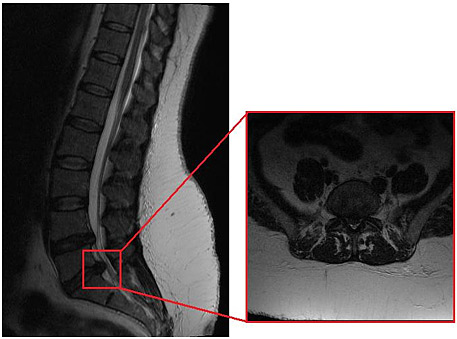

Εικ 4.

Μαγνητική τομογραφία: μεγάλη κεντρική δισκοκήλη Ο5-Ι1 με συμπίεση των νωτιαίων ριζών